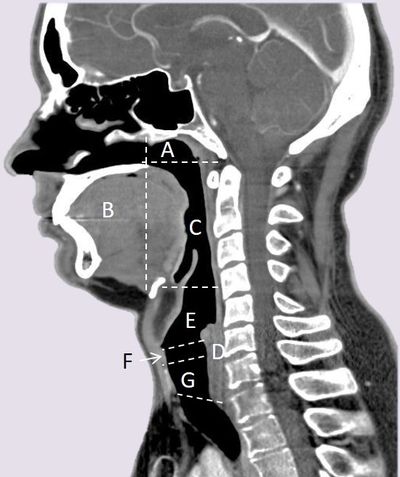

-- 1. Posterior Wall

-- 2. Pyriform Sinus (2)

-- 3. Post-cricoid

-- (4.) Posterior confluence of aryepiglottic folds